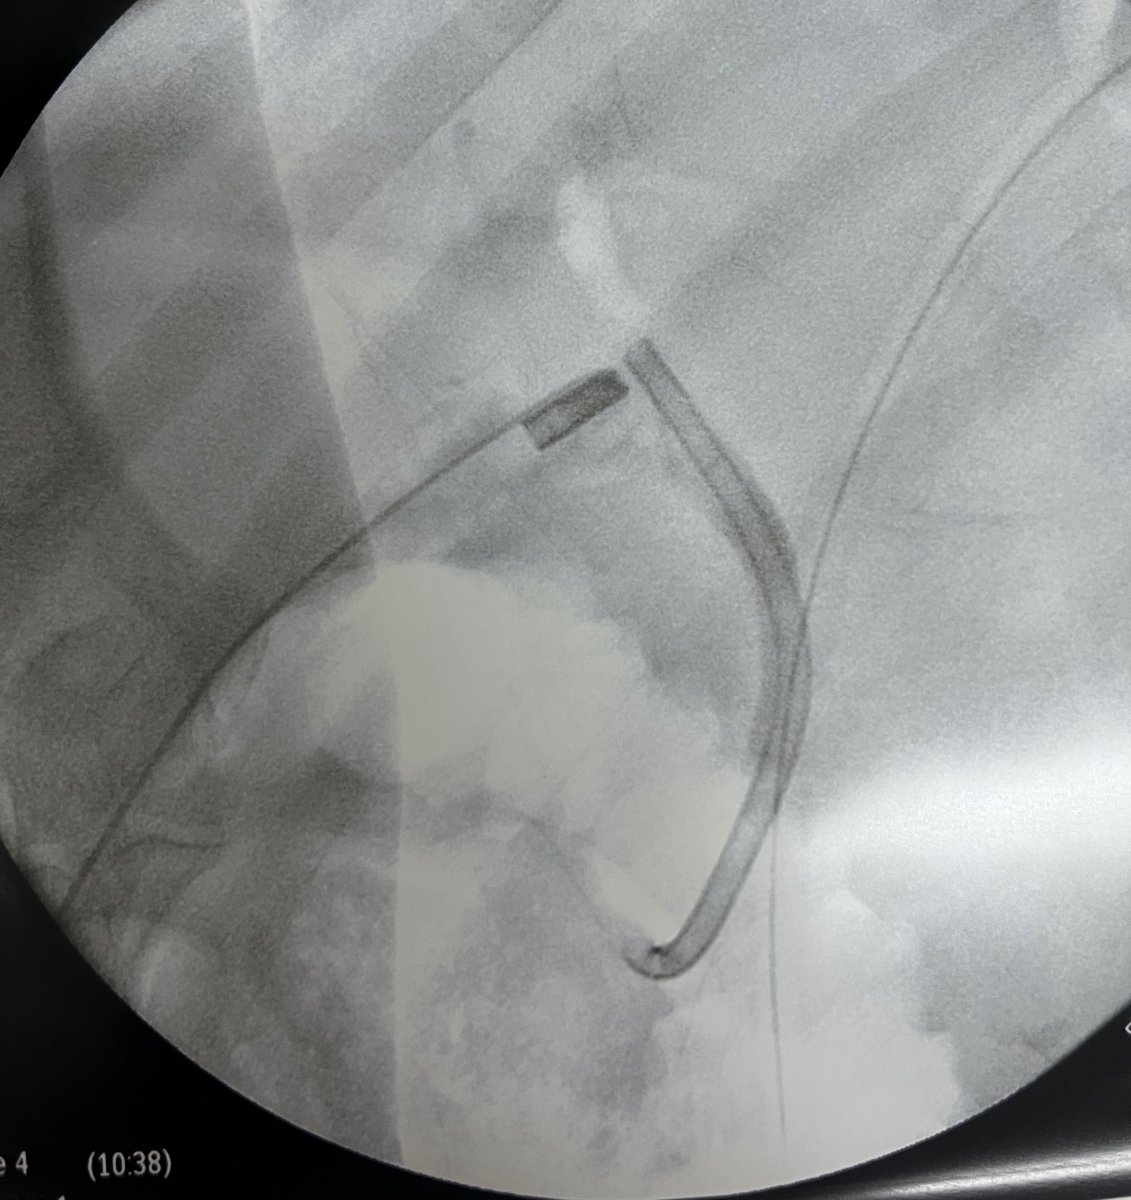

⚡️Tips to improve lift for resection⚡️

4. >30: inject, cut, repeat

Agents:Fig